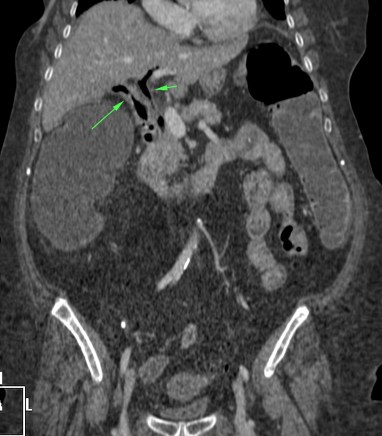

Se realiza un TC abdominal sin contraste:

Observar como posterior a la litiasis hay un cambio de calibre, el segmento que queda de ileon y el colon no están distendidos.

No encontramos ante un Ileo biliar, una obstucción intestinal mecánica ocasionada por una litaisis enclavada en el íleon terminal. La paciente estaba colecistectomizada, por tanto, lo más probable es que haya sido producido por una litiasis residual que pasó desapercibida.